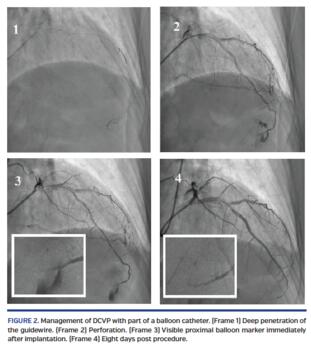

Method of implementation and the case registry. Management of DCVP with part of a balloon catheter is illustrated in Figure 1 and Figure 2. The technical steps are as follows: (1) immediately apply prolonged balloon inflation (PBI) to stop extravasation; (2) cut the previously expanded balloon in the middle of the length between the markers; (3) place the proximal fragment of the umbrella-shaped balloon on a guidewire; (4) place another uninflated balloon (the “pushing balloon”) on the same wire; and (5) push part of the cut balloon to the distal part of the vessel using the second pushing balloon and place it in the distal vessel to embolize before the place of perforation.

If the perforation cannot be closed with one part of the balloon, the operation can be repeated with the next bigger size of cut balloon.